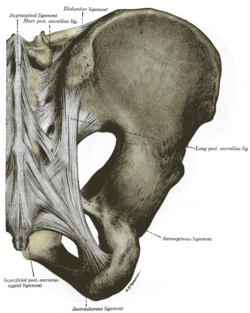

Articulations of pelvis. Posterior view. | |